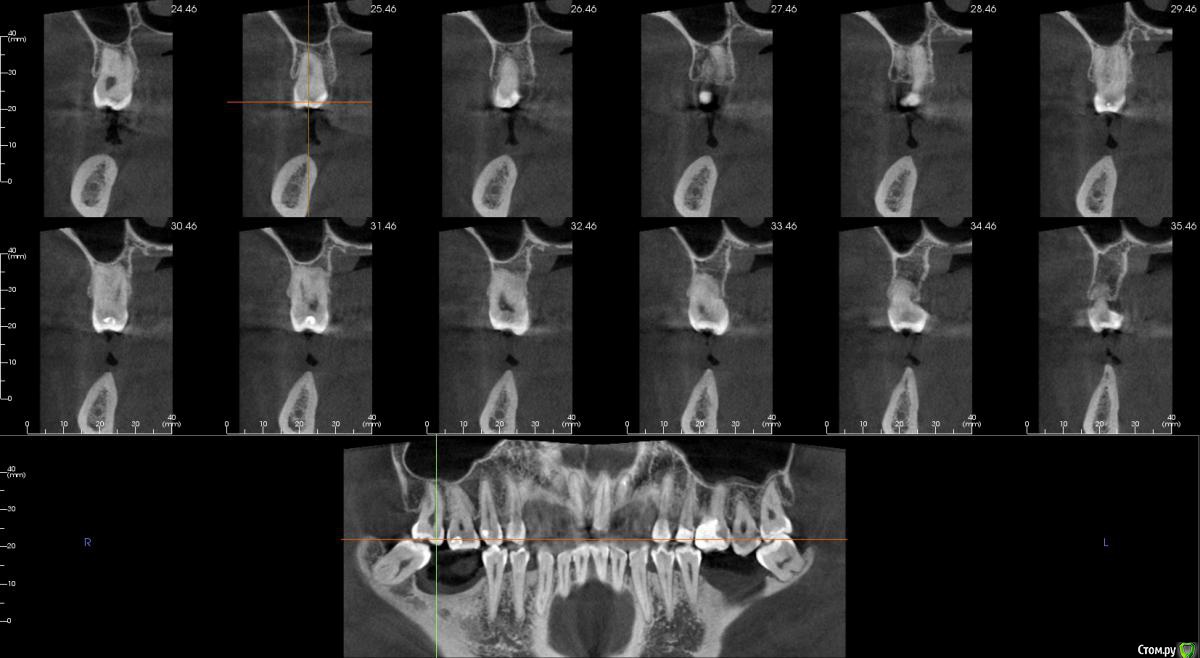

Господа как лучше тут поступить? поменьше бы рисков)

" всеводинэтап"крыша гаража" и латерализация отменяются)))

вижу вариант только с сеткой.

Из того что разобрал по срезам мне кажется можно медиально расщепить и притопить, дистально 4х6 поставить (астра, штрауманн...). Посмотрите, помещаются ли такие импланты. Травма меньше, быстрее и меньше рисков.

Сделайте нкр с медиальными болтами, дистальные глубже установите.

Тогда десну аля шашлычки и фдм отсроченно.

Далее временное протезирование.